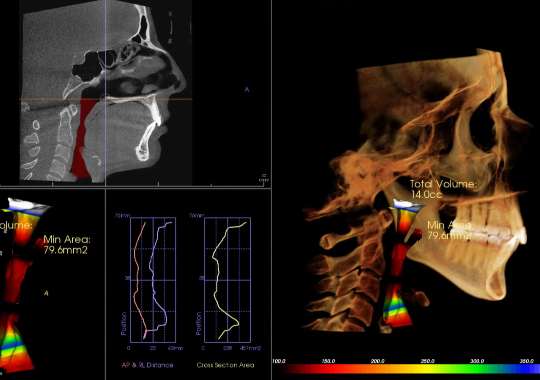

Exámen de Via Aérea Volumetría

Mediante el CBCT podemos analizar la vía aérea en toda su extensión tanto anteroposterior como lateral,

Lo que nos permite evaluar factores de riesgo para desarrollar OSA y predictibilidad de algunos tratamientos